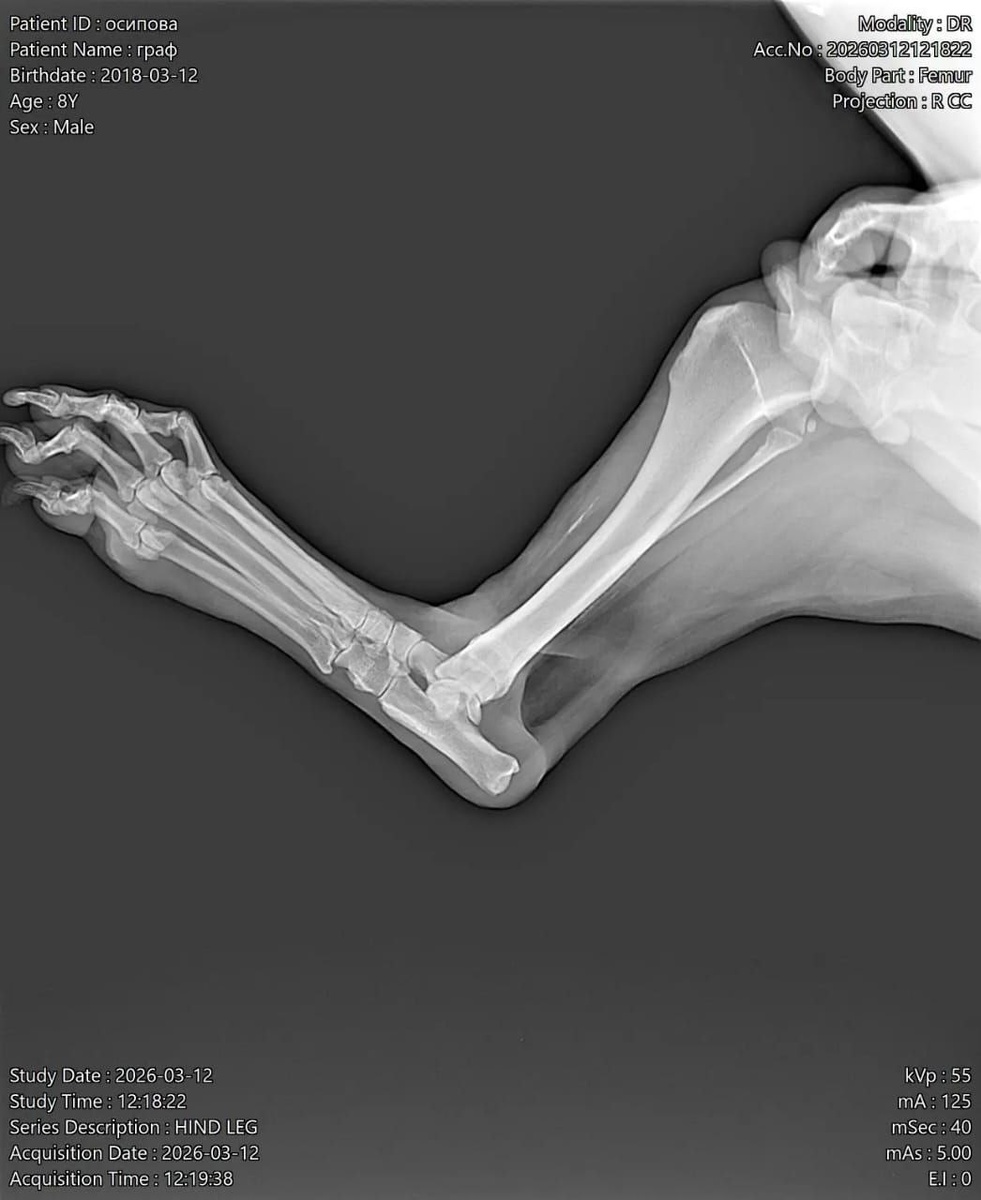

Старичок Граф несколько дней назад начал грызть заднюю лапу. Это говорит о том, что лапа у собаки болит.

Снимок лапы Графа

Осмотр в клинике и рентгеновский снимок показал прогрессирующий артроз. Назначен курс лечения и внутривенные уколы гиалувита.